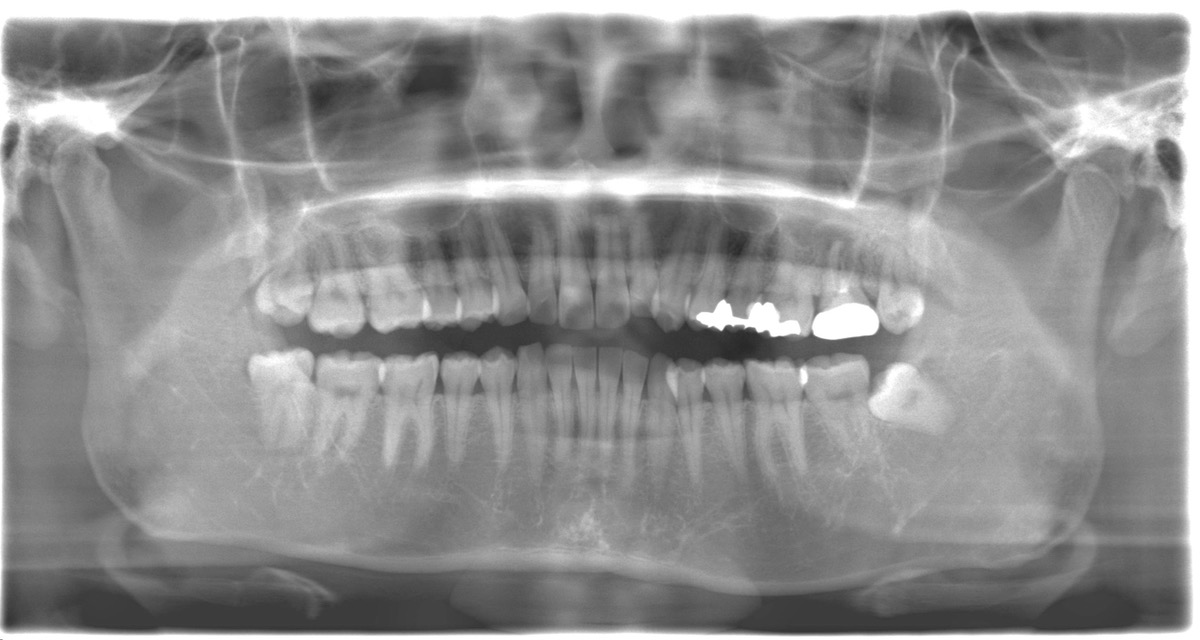

左上の奥歯が膿んでしまい、抜く必要があると前医で言われたが、骨がないからインプラントは難しいと言われてしまった相談に来られた【50代女性】

ご相談内容 左上奥歯が膿んでしまい、前医で「抜歯が必要」「骨が少なくインプラントは難しい」と言われ不安になり相談に来院